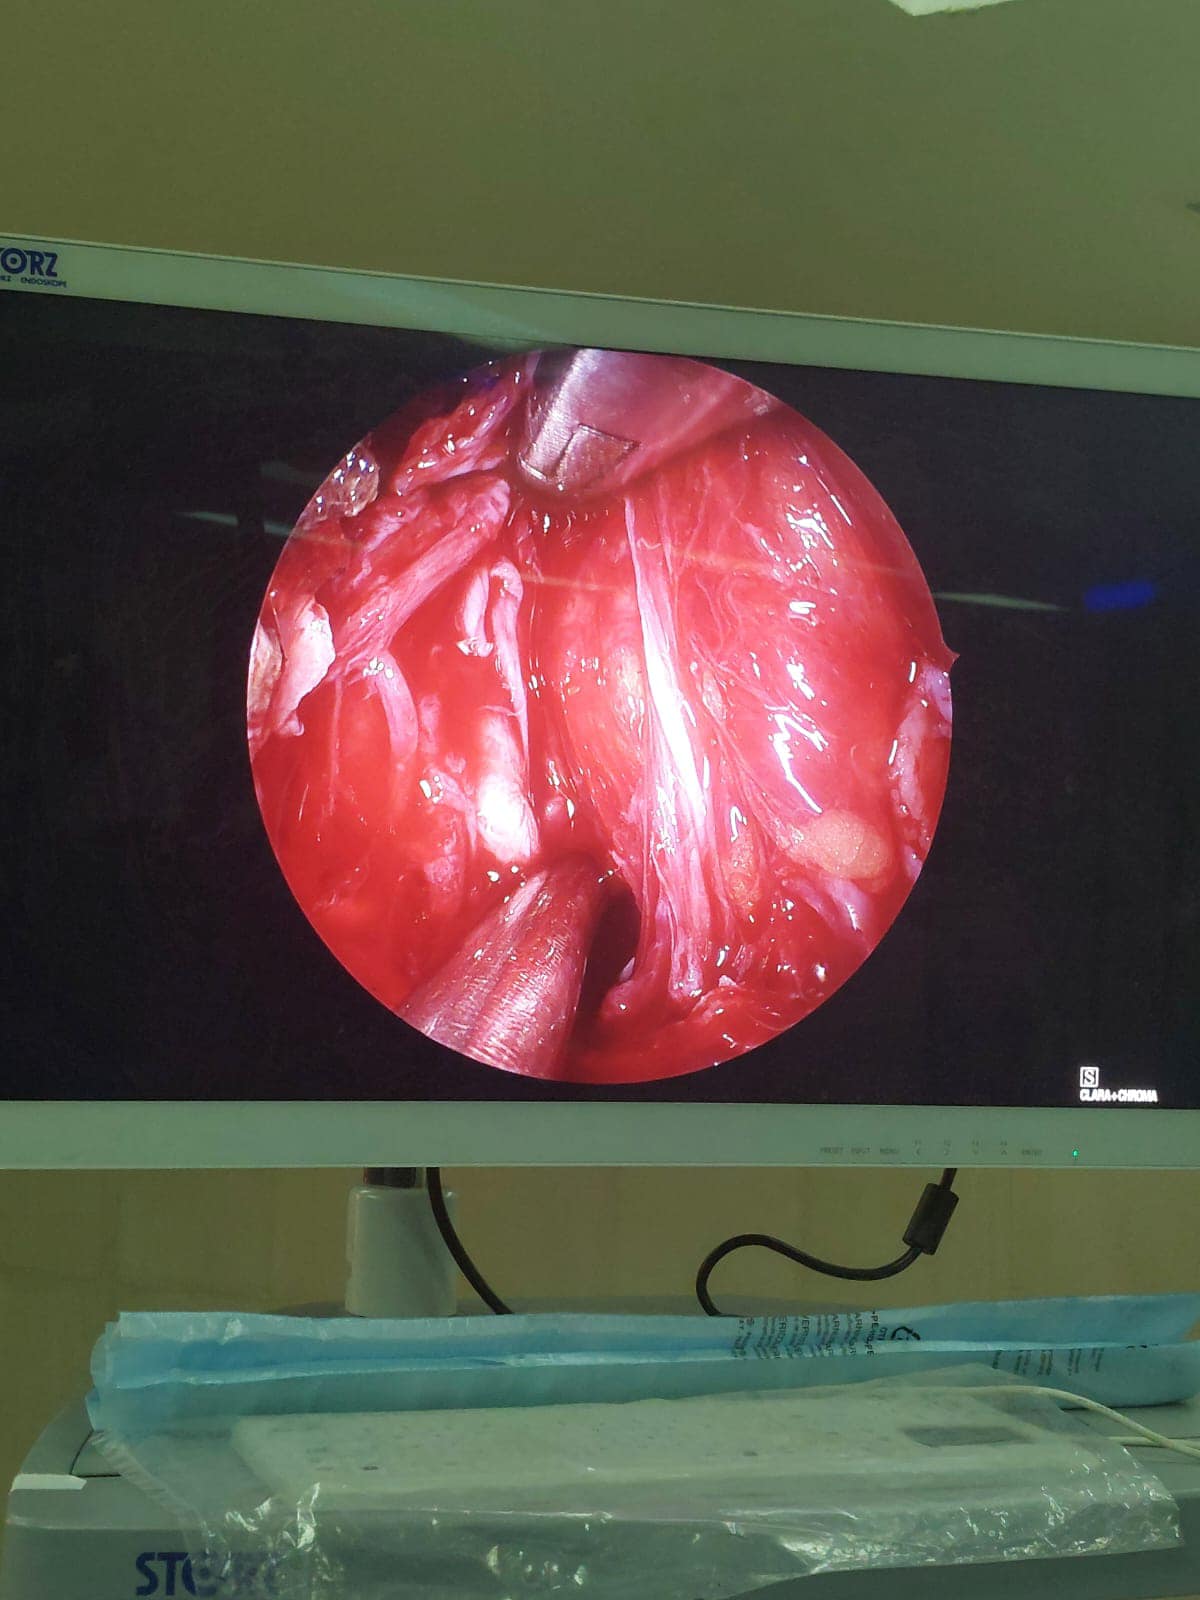

الجامعي من استئصال ورم دموي (انجيوفيبروما) بالأنف ممتد إلى الجيب الأنفي الوتدي و ملتصق بالشريان السباتي وممتد إلى المخ، لشاب في مقتبل العمر ١٦ سنة يدعي “ج. ع. ف” بمركز المنشاه، وذلك في عملية استغرقت ٥ ساعات متواصلة.

ومن جانبه أضاف الدكتور محمد عبدالقادر سلطان رئيس قسم الأنف والأذن والحنجرة، أنه علي الفور تم تشكيل فريق طبي علي درحة عالية من المهارة نظراً لخطورة العملية ودقتها، فتم حقن الشرايين المغذية للورم الدموي قبل العملية لتقليل النزيف اثناء العملية بالأشعة التدخلية، وعقب العملية خرج المريض في حالة صحية مستقرة.

جدير بالذكر أن الفريق الطبي الذي أجري العملية بسرعة ومهارة عالية بقسم الأنف والأذن والحنجرة برئاسة الدكتور ابراهيم رزق محمد، ضم كلاً من الدكتور عرفات محمود محمد، والدكتور محمد عبدالمتين موسي، والدكتور فرغلي عبدالرحمن، والدكتور محمد عبد السميع مدرس مساعد، والدكتور محمد سلطان طبيب مقيم، بينما تشكل فريق التخدير برئاسة الدكتور فوزي عباس وضم كلاً من الدكتور هيثم محمد اسماعيل، الدكتورة منار زكريا، ومن قسم التمريض مستر محمود عبدالرازق، ومستر احمد مصطفى.